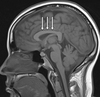

1

Q

A

quadrigeminal cistern